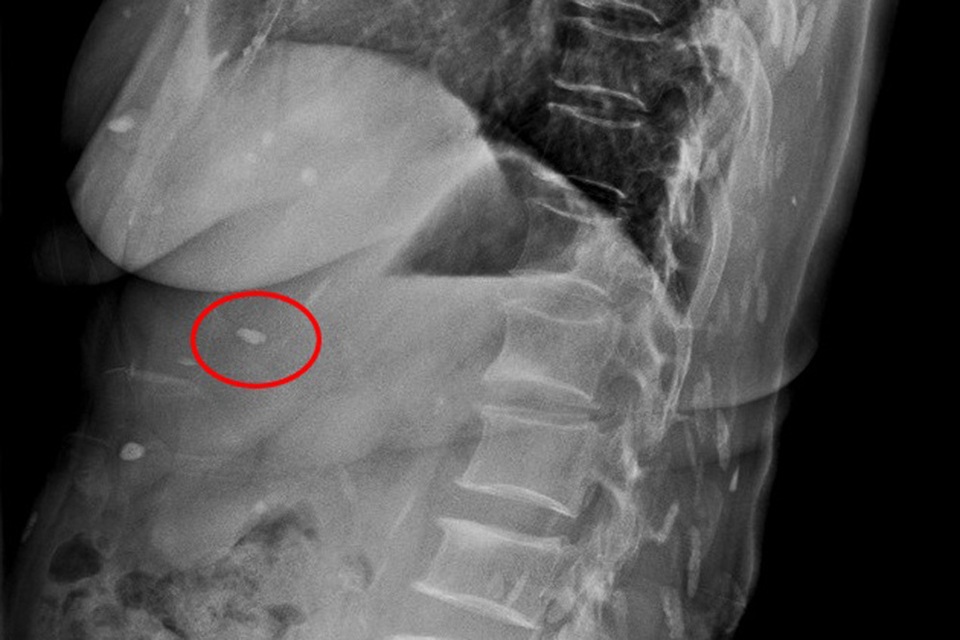

Hình ảnh cho thấy rất nhiều con sán lá gan (màu trắng) ký sinh dọc cột sống |

Qua thăm khám, các bác sĩ xác định bệnh nhân bị mắc bệnh sán lá gan sinh sống trong cơ thể nhiều năm, đang sinh sôi, lan ra trong nhiều bộ phận cơ thể.